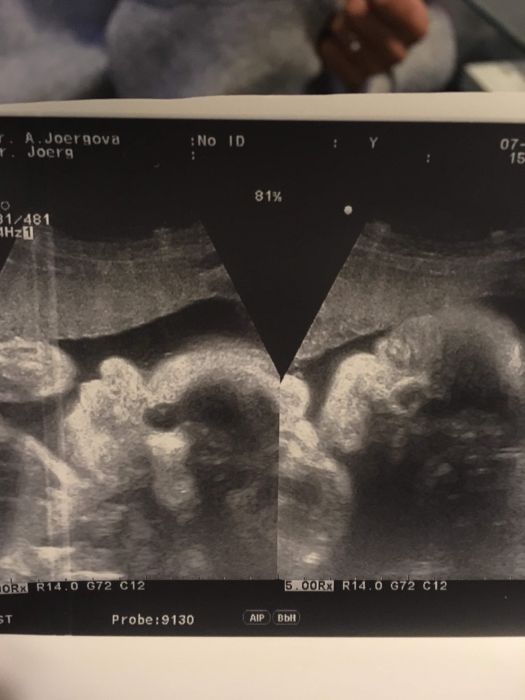

Tak se holky hlásím po kontrole vše v pořádku Ríša se má čile k světu . Zatím to teda na nějakého drobečka prý nevypadá .. váhový odhad 1300-1500g , ale budu to brát s rezervou než se stresovat dopředu :-D jinak ř přidávám fotečku a kontrola zase za měsíc ..